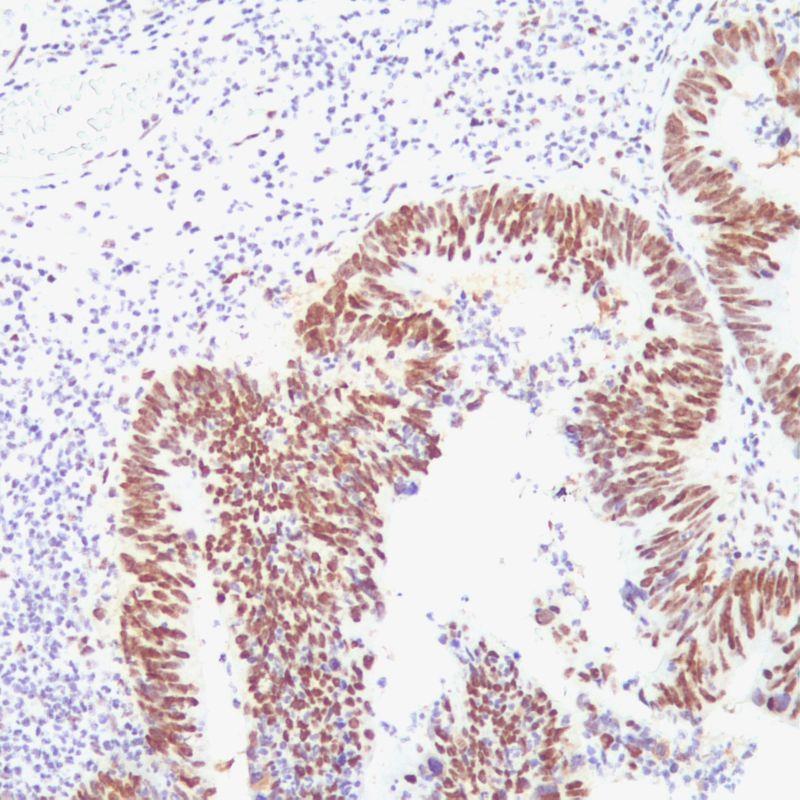

MSH2 Antibody (Immunohistochemistry)

MutS Homolog 2 (MSH2) is a protein involved in the mismatch-repair pathway. This protein is commonly associated with hereditary non-polyposis colorectal cancer, and mutations in this gene are correlated with the development of sporadic colorectal carcinoma. Expression levels of MSH2 are abnormally low in a high percentage of patients with microsatellite instability, as well as endometrial and ovarian cancers. Use of Anti-MSH2 is optimized when paired in an IHC panel with antibodies against MSH6, MLH1, and PMS2. Reports have shown Anti-MSH2 to be useful in the detection of the protein in a number of normal and neoplastic tissues, and for identifying a loss of MSH2 in tumours that are microsatellite-unstable. Add the primary antibody to bind the antigen on tissue sections, and then use HRP labeled secondary antibody binding primary antibody to form the secondary antibody-primary antibody-antigen complex. When DAB chromogenic solution is added, HRP reacts with enzyme substrate to produce brown insoluble reaction product, which indirectly indicating the existence of antigen.